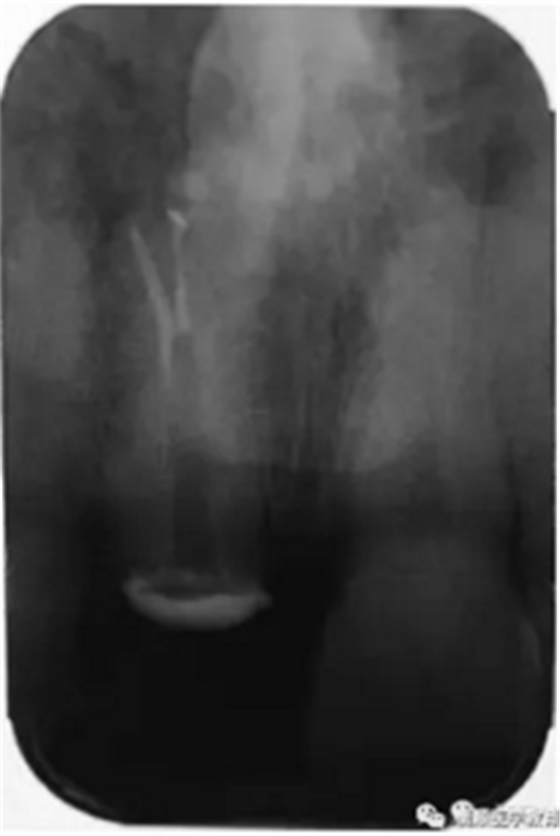

基于臨床檢查和X線片顯示,診斷為右上頜中切牙根尖周炎伴額外牙。治療計劃是先行患牙的根管治療,制作臨時義齒,最后制作樁核冠。應(yīng)用橡皮樟和顯微根管技術(shù),利用ProTaper旋轉(zhuǎn)銼配合使用 Hedstrom 銼和桉葉油,將根管內(nèi)充填物取出,觀察X線片可見根尖三分之一處主根管一分為二,確定另一根管的工作長度,兩根管同行常規(guī)根管治療,充填后X線片顯示根管充填良好。樁核冠修復(fù)1年后,患牙無疼痛,影像檢查發(fā)現(xiàn)根尖顯影正常,根尖疾病治愈。

圖2. 患牙根管充填后即刻X線片顯影